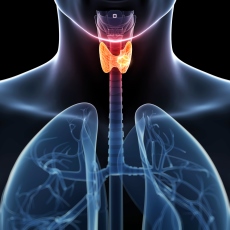

• Disfunciones tiroideas